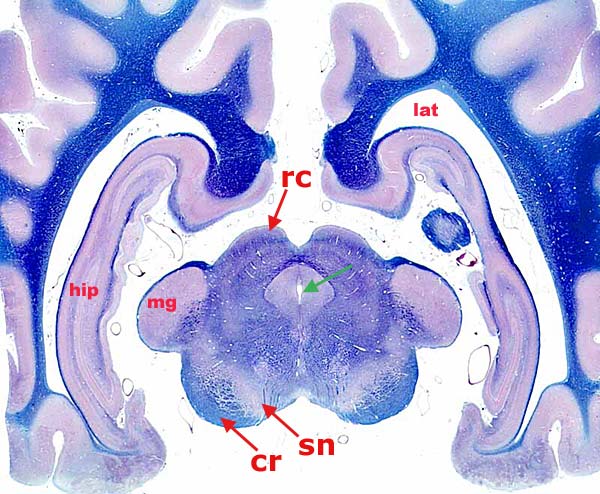

Canine Midbrain Transection

Transverse section through a canine midbrain that is surrounded by telencephalon (white matter is stained blue). The mesencephalic aqueduct (green arrow) is surrounded by periaqueductal gray matter. The midbrain region that is dorsal to the aqueduct is designated tectum. The rostral colliculus (rc) is within the tectum. The region immediately ventral to the tectum is called tegmentum. Ventral to it, observe the substantia nigra (sn) and crus cerebri (cr).

Labeled non-mesencephalic structures are: medial geniculate (mg), hippocampus (hip), and lateral ventricle (lat).